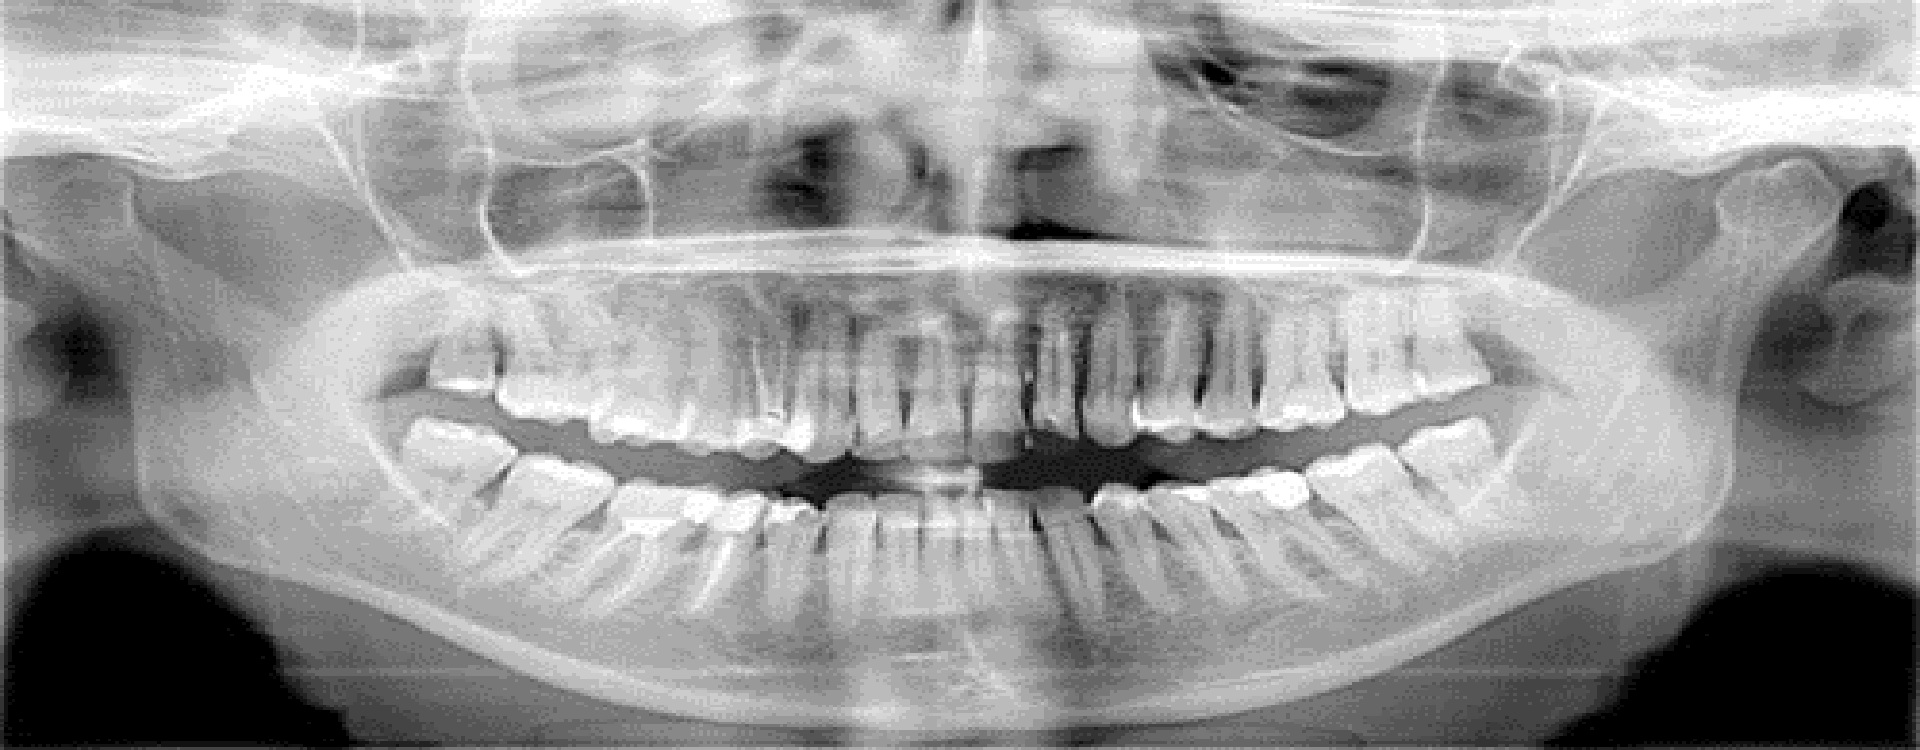

Digital Opg

Panoramic And Cephalometric Imaging CS 8100

An ideal blend of simplicity and sophistication, the CS 8100 truly redefines panoramic imaging. Designed to make your daily work easier and more intuitive, the system features a variety of tools to make positioning easier, image acquisition faster, and higher image quality more accessible—exactly what you need to streamline your workflow, improve usability, and make more accurate, real-time diagnoses. For even more imaging options, take advantage of the CS 8100SC system—our all-new option that combines both panoramic and cephalometric imaging.

Sharp, High-Quality Images

High-frequency generator ensures radiation remains constant for optimal contrast An advanced Active Pixel CMOS sensor, vibration-free motion system, and 0.5 focal spot make it easy to capture highly detailed, contrasted, and crystal-clear images in seconds Powerful artifact-free filters enhancing contrast and sharpness with a single click